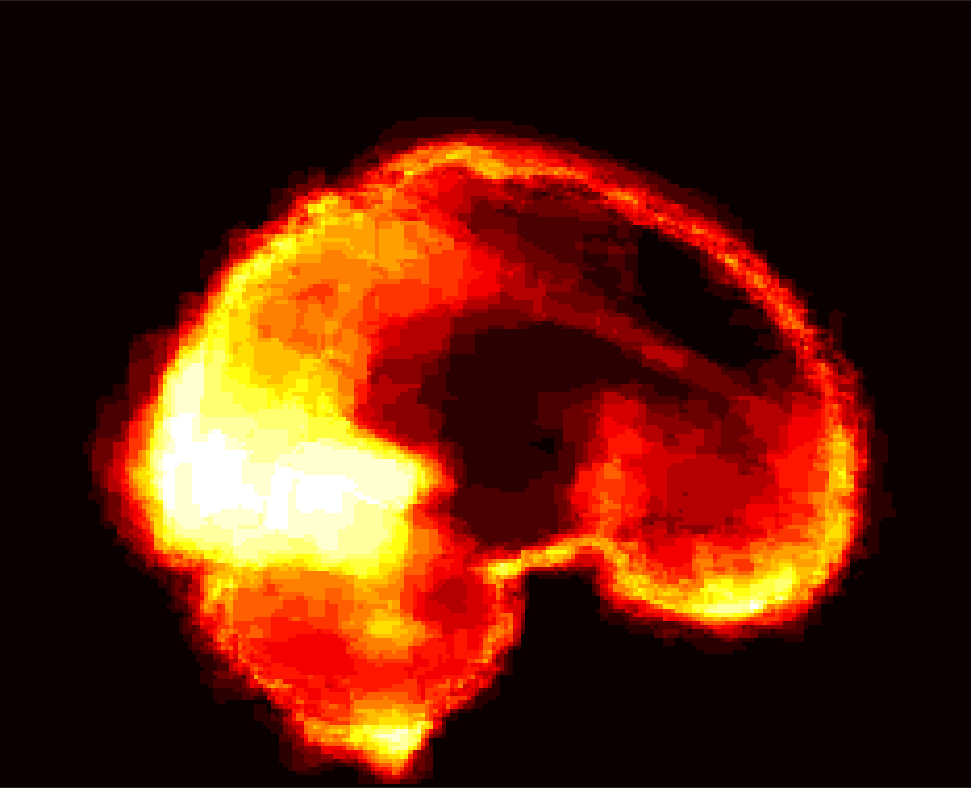

[Uncaptioned image] [Uncaptioned image] [Uncaptioned image] [Uncaptioned image]

(a) (b) (c) (d)

Figure 8: Example BRATS image with its decomposition result in atlas space. (a) Input image after pre-processing; (b) quasi-normal image L+M𝐿𝑀L+M; (c) non-brain image S𝑆S; (d) pathology image T𝑇T.

In addition to extracting the brain from pathological datasets, our method also allows for the estimation of a corresponding quasi-normal image in atlas space, although this is not the main goal of this paper. Fig.8 shows an example of the reconstructed quasi-normal image (L𝐿L) for an image of the BRATS dataset, as well as an estimation of the pathology (pathology image T𝑇T and non-brain image S𝑆S). Compared to the original image, the pathology shown in the quasi-normal image has been greatly reduced. Hence this image can be used for the registration with a normal image or a normal atlas. This has been shown to improve registration accuracy for the registration of pathological images [27]. Furthermore, an estimate of the pathology (here a tumor) is also obtained which may be useful for further analysis. Note that in this example image the total variation term captures more than just the tumor. This may be due to inconsistencies in the image appearance between the normal images (obtained from OASIS data) and the test dataset. As our goal is atlas alignment rather than quasi-normal image reconstruction or pathology segmentation, such a decomposition is acceptable, although we could improve this by tuning the parameters or applying regularization steps as in [27].